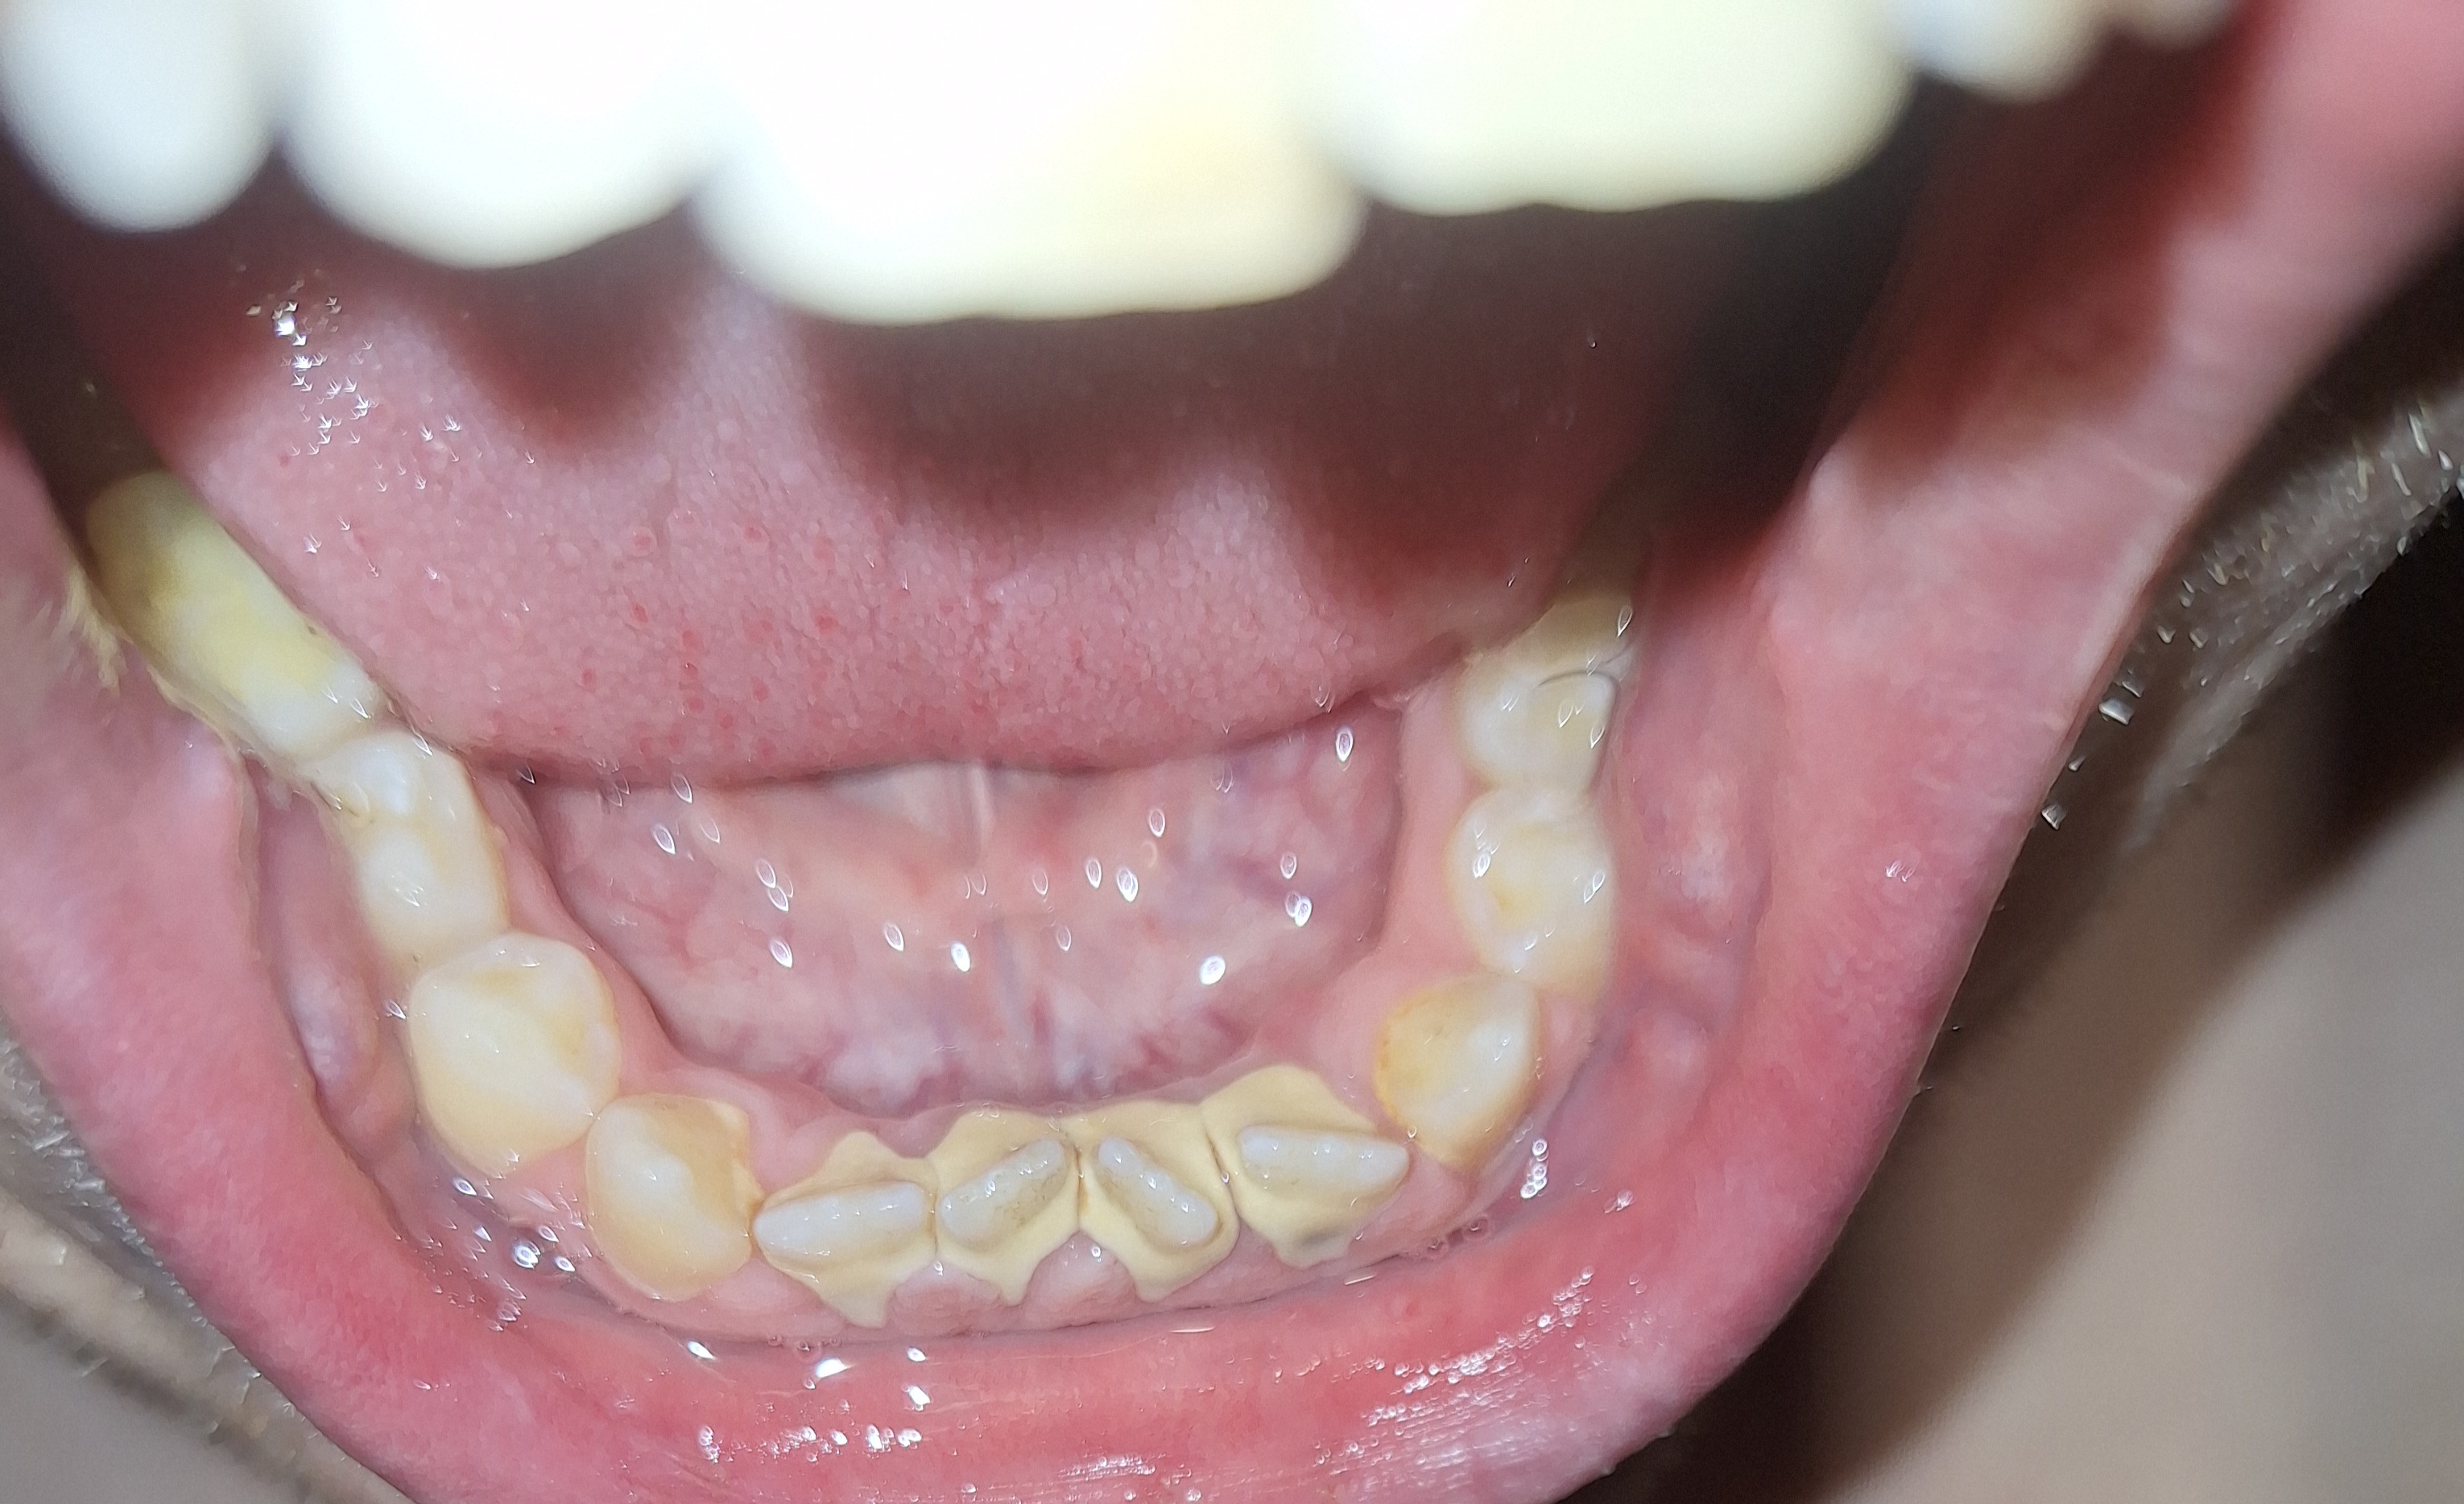

Ну че, у самого уже парадонтит, т.е нихуя не поможет, снизу зубы уже пиздец десна опустилась, сверху пару выпало просто что держаться не могут

Аноним 26/02/25 Срд 04:48:31 1604841 29